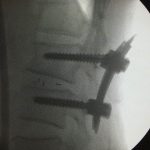

After the operation, he is now happily receiving the help of the lower back screws!